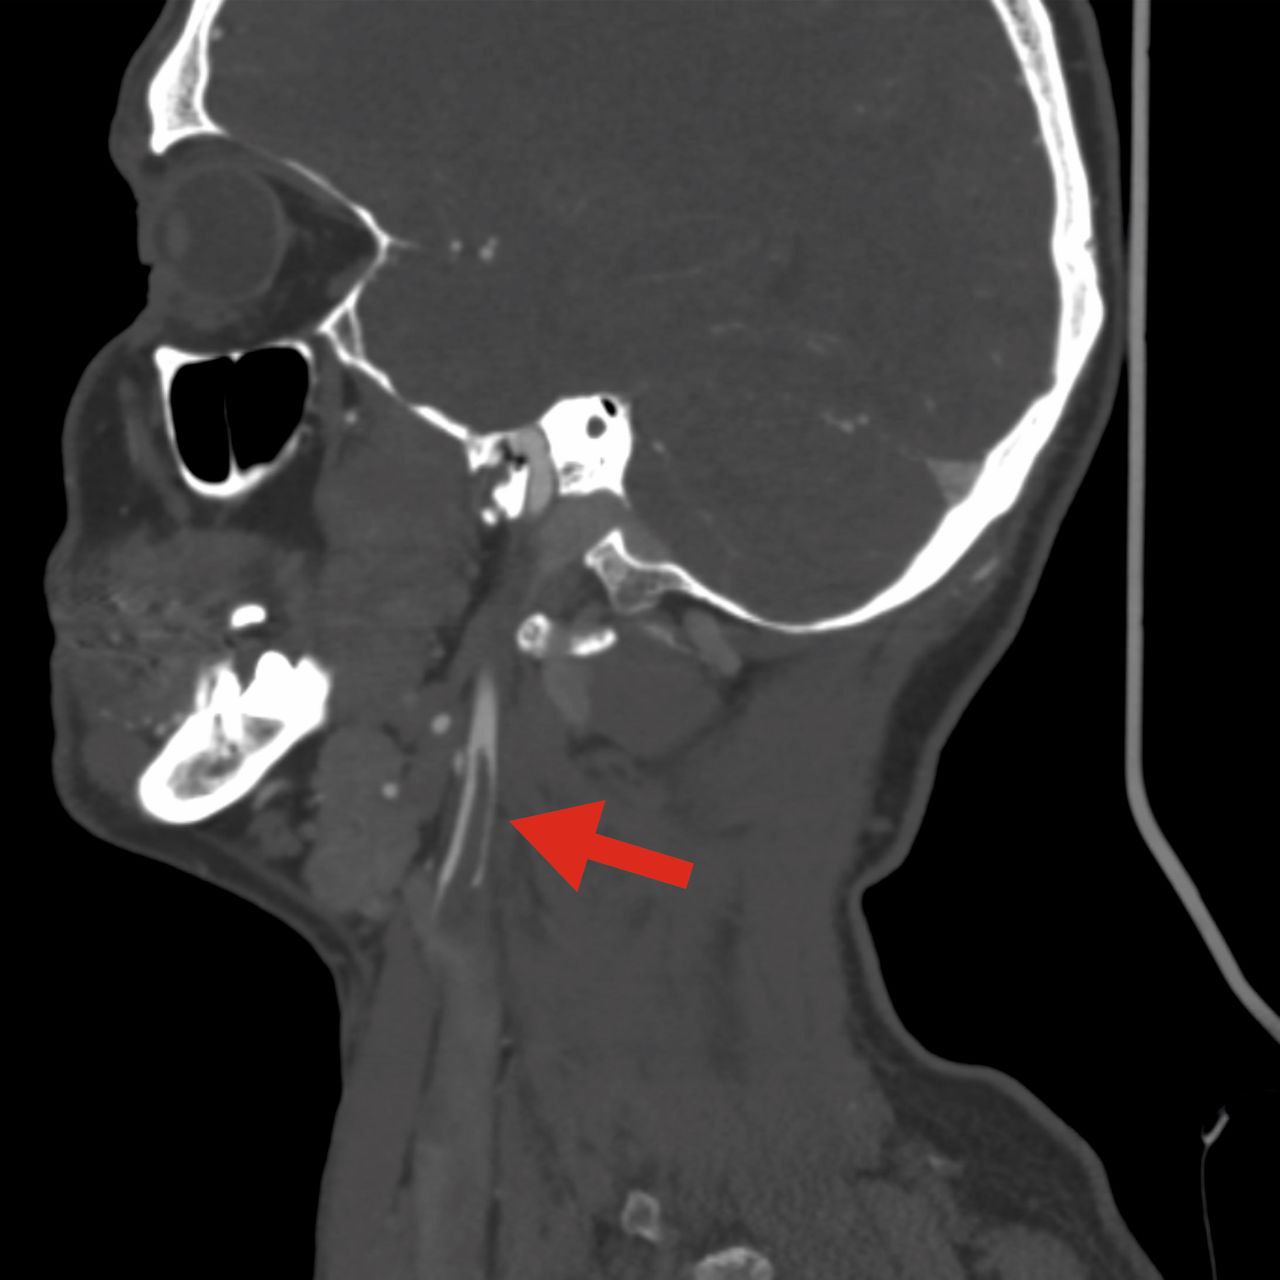

В приемное отделение экстренно доставилт пациента 1979 года рождения с жалобами внезапную слабость и онемение в левых конечностях. Обследование выявило флотирующий тромб длиной до 4 см в просвете правой внутренней сонной артерии. Тромб создавал препятствие кровоснабжению головного мозга и мог оторваться, что привело бы к обширному ишемическому инсульту.